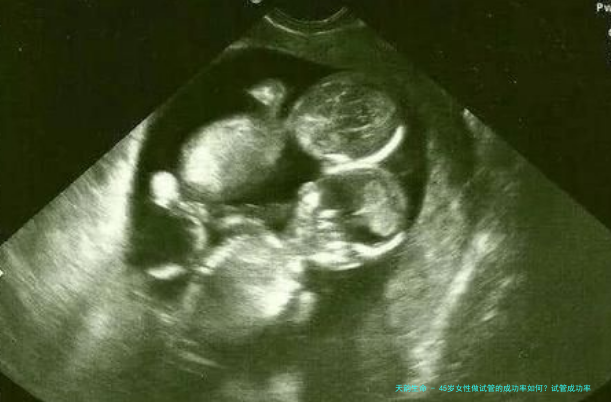

四十五岁女性进行试管受孕(试管婴儿(IVF))的成功率相应偏低,但并不是不可能。年纪是影响试管婴儿成功率的首要要点其中之一,特别是关于四十五岁的女性来讲,卵巢机能和卵子质量平常会有所减少,这直接影响了胚胎质量和着床率。

研究阐明,四十五岁左右的女性进行试管婴儿的成功率大致在1%到5%之间。这个数字尽管不高,但也表示还有成功的可能性。详细成功率还取决于于许多种要素,囊括个别的体质状况、卵巢功效、子宫腔内环境以及医生的经验和技术造诣。